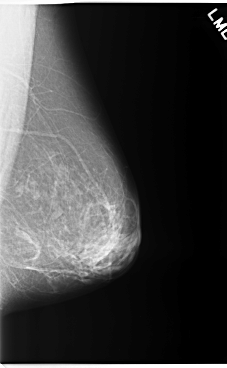

C_0255_1.LEFT_CC

LEFT_CC LINES 5912 PIXELS_PER_LINE 3560 BITS_PER_PIXEL 12 RESOLUTION 50 NON_OVERLAY